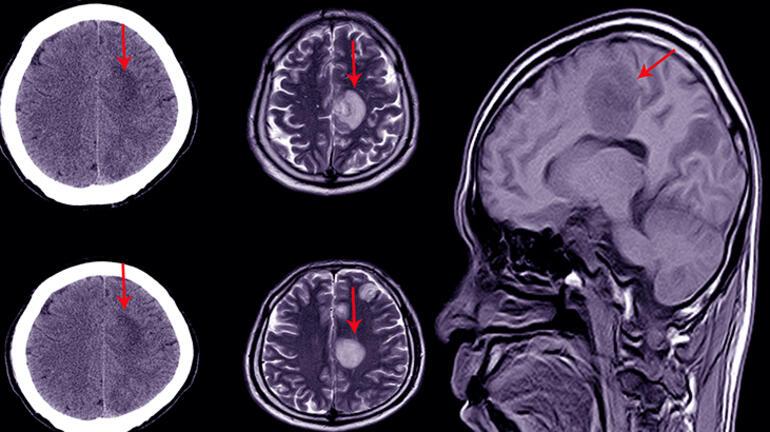

Kalp krizi geçirdikten sonra hayata dönen toplamda 567 kadın ve erkek hasta üzerinde yapılan araştırmalarda ilk olarak 53 kişinin tepkileri izlendi. Araştırmacılar, hastaların beyinlerine bir izleme cihazı taktı. Bu izleme cihazı sayesinde beyinlerinin bilgi alıp almadığına dair bir sinyal olup olmadığı takip edildi.

Hastalar tedavi edilirken bir yandan da önlerine bir ekran konuldu. ‘Elma’, ‘armut’ ve ‘muz’ gibi basit kelimeler 5 dakikada bir hastalara sesli klip olarak hastalara dinletildi, bu sesli klibe sözcüklere ait görseller de eşlik etti. Bu kişilerden ikisi kalp masajı esnasında sağlık görevlilerini duyduklarını hatırladı, bazıları ise kendilerini bir eve doğru yürürken gördüklerini söyledi.